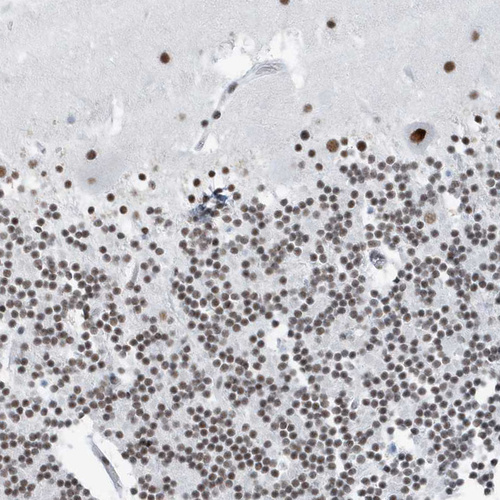

Immunohistochemical staining of human testis shows strong nuclear positivity in cells in seminiferous ducts.